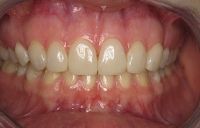

Na de behandeling met composiet

Door het composiet is er weer een dikke, stevige laag ontstaan aan de binnenzijde die niet snel zal afbreken. De tanden zijn hierdoor ook weer verlengd.